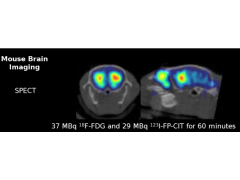

型号:SPECT/CT

1. SPECT参数

1.3 分辨率:小鼠全身最高分辨率是0.25mm;